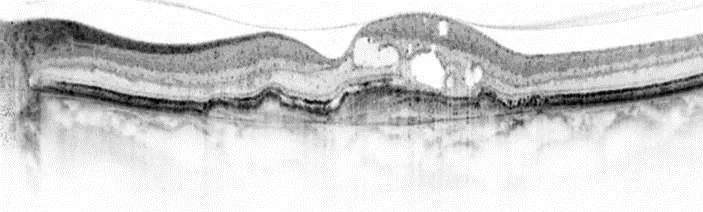

Optische Kohärenztomographie bei neovaskulärer altersabhäniger Makuladegeneration. optische-kohaerenztomographie.webp image/webp Typ image/webp Dimension Abmessungen 703x212 Size Dateigröße 25.8 KB Herunterladen Bild in voller Größe anzeigen…